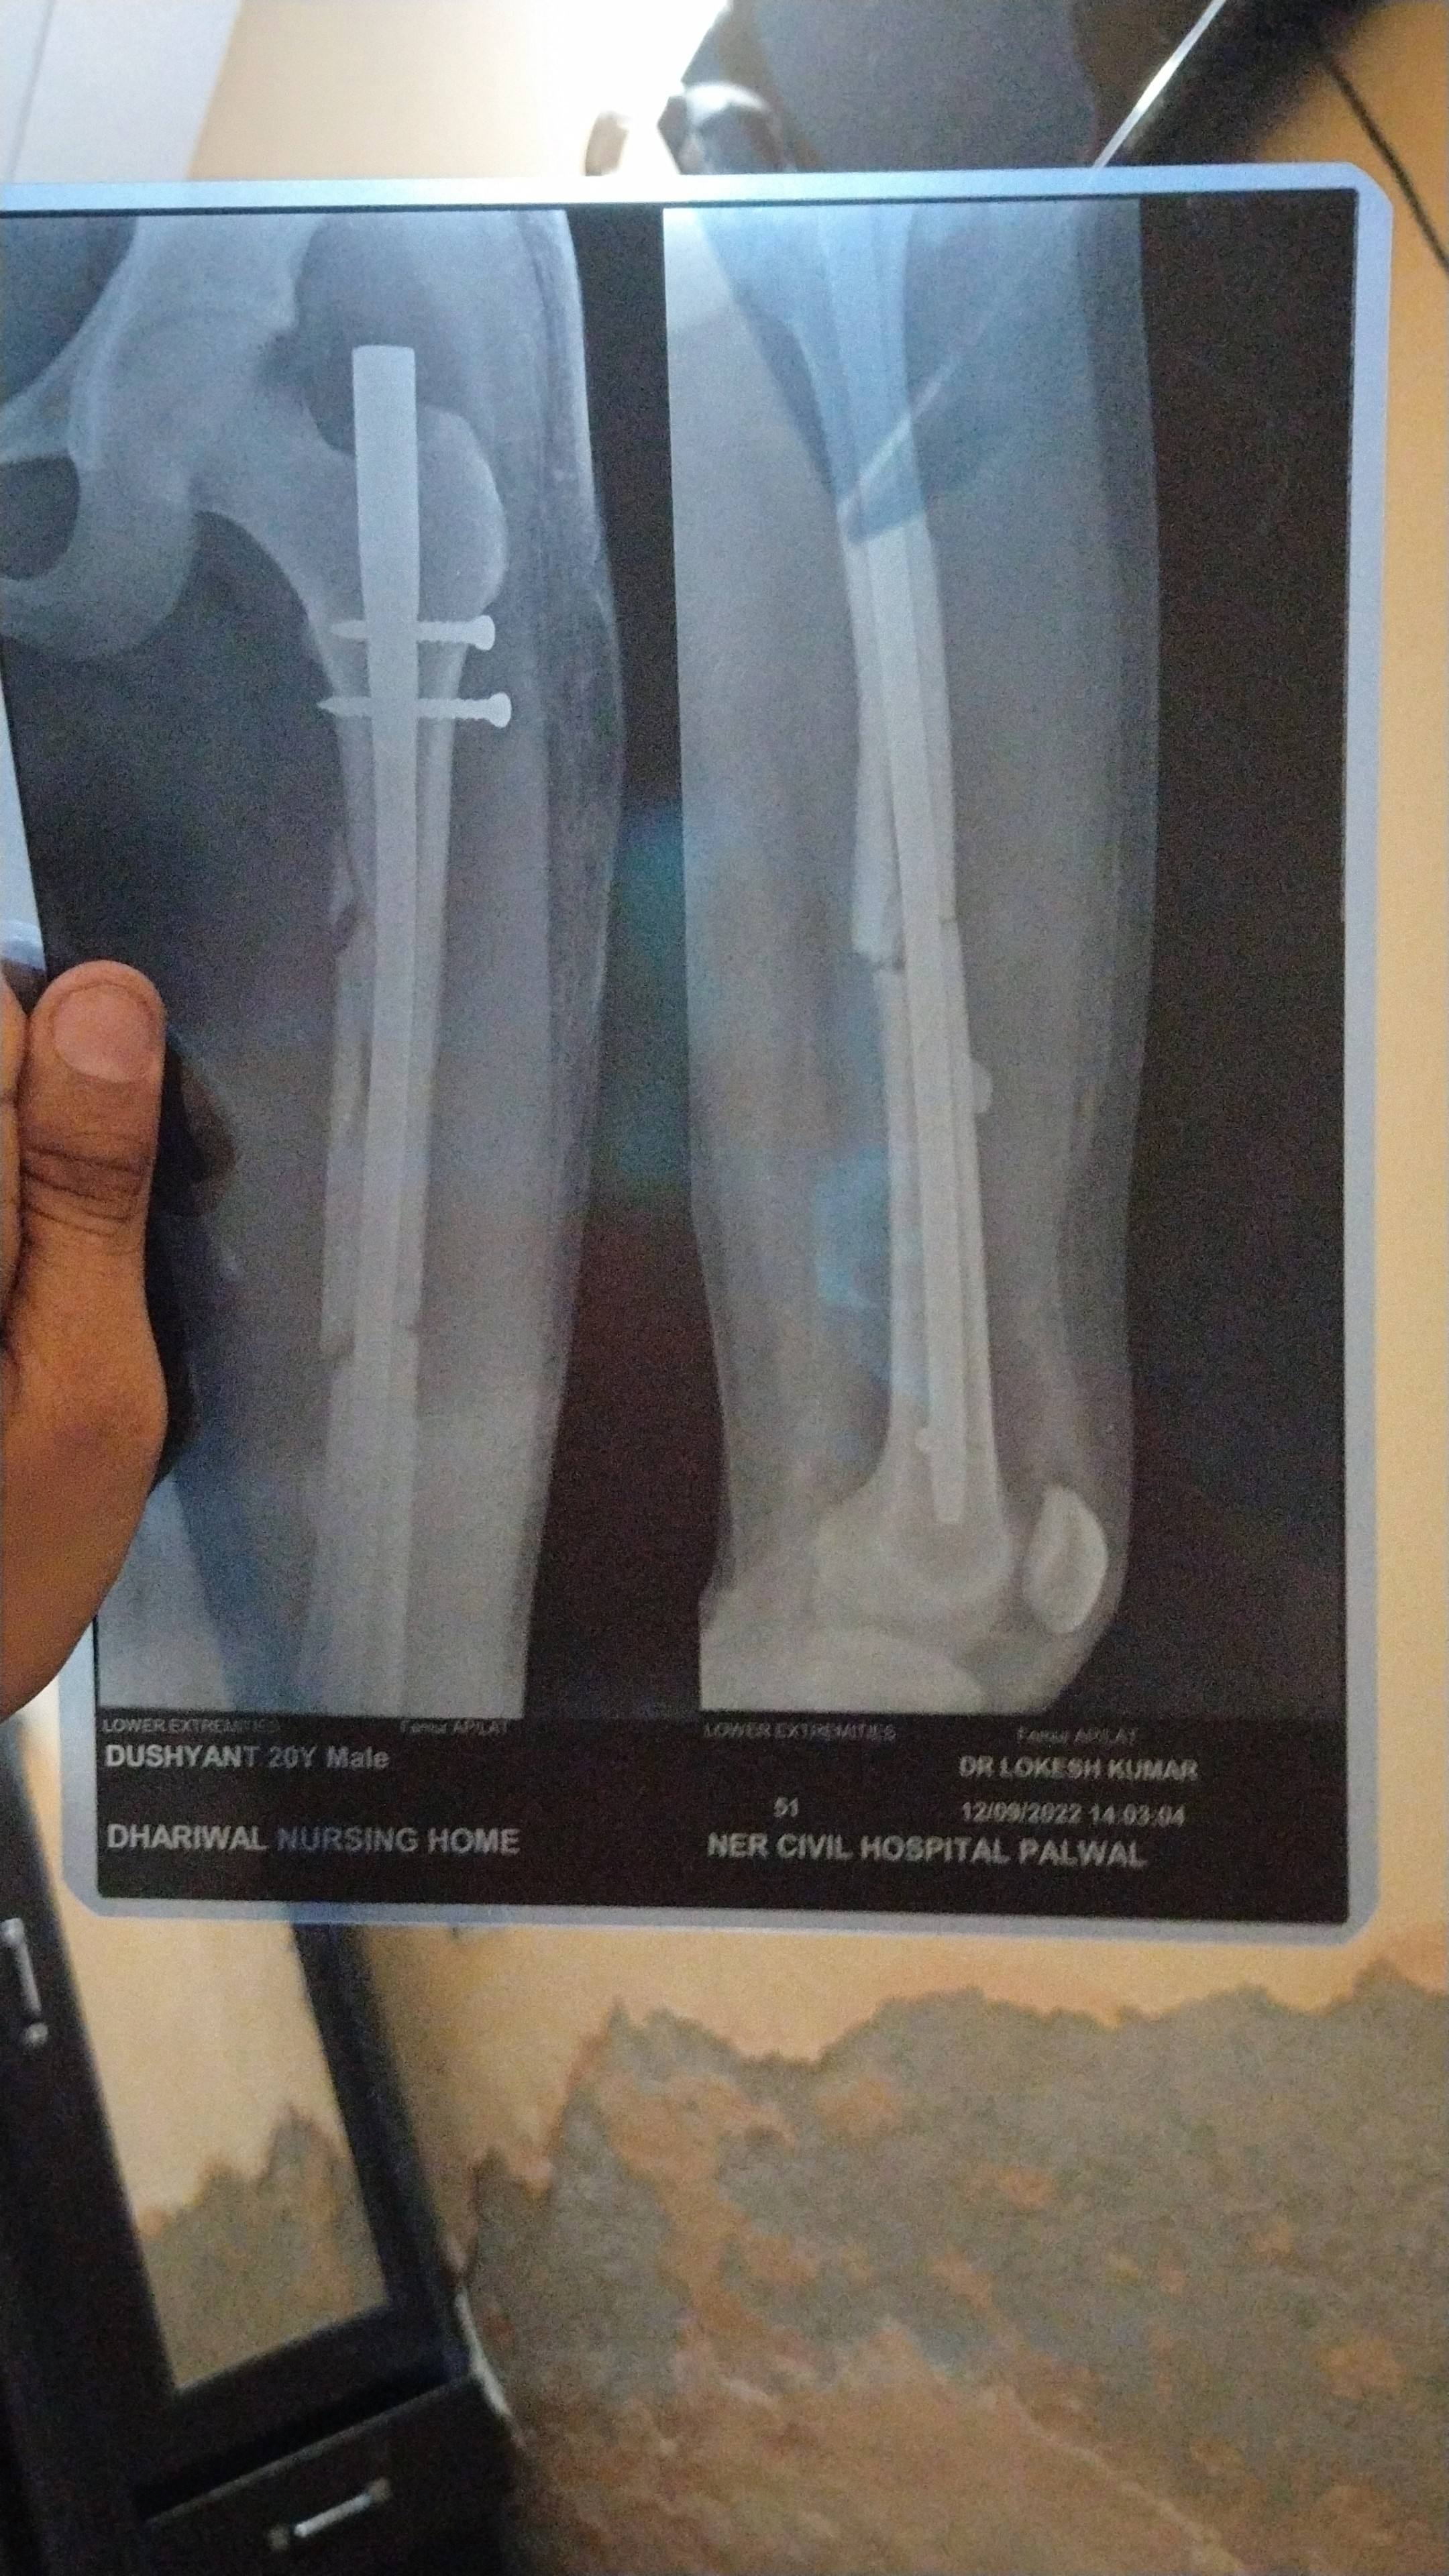

myself Dushyant from palwal Haryana .sir mera 8 august ko femur bone shaft fracture   hua tha jisme aur bone displace ho gyi thi air overlap bhi the  10 august ko meri successful surgery hui thi aaj mujhe 78 dsys ho chuke hn i m walking with full weight bearing with walker then how much time this bone takes to heal completely and whenn i am able to walk normal activities likea normal person helo me sir my surgeon is non responsable i come with a great hope to you ?may god bless you a prosperious life

sir for m kab se activities start kr skta hu kunki or doctor bta rhe the ki isme 2 mhina lgega mtlv 2 mhine ho gye 2 or lgenge ye completely heal ho jaega

it will heal in 4 to 5 months . walk daily. More walking will help in faster healing.